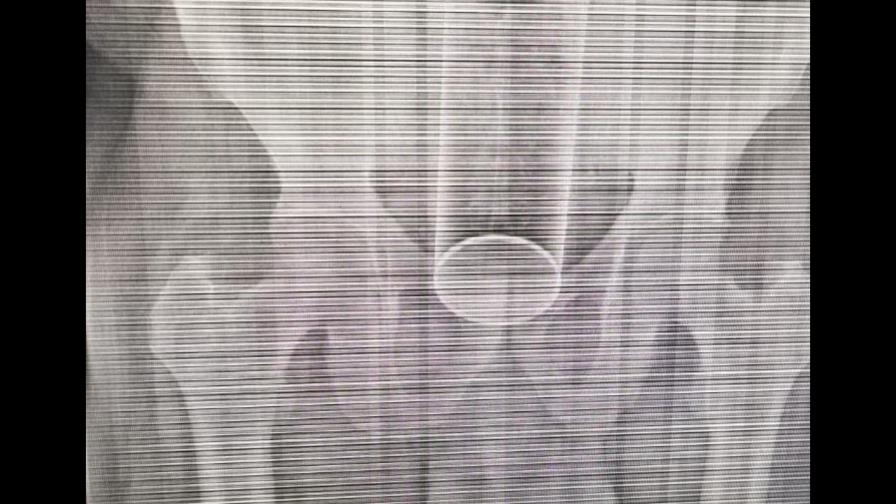

Un hombre fue intervenido quirúrgicamente luego de que se le alojara un frasco de insecticida en el recto mientras sostenía relaciones sexuales con su pareja.

El hombre, de 40 años, llegó al hospital Moscoso Puello con el objeto alojado en el recto, según informó el relacionista del centro asistencial, Hanobi Delgado.